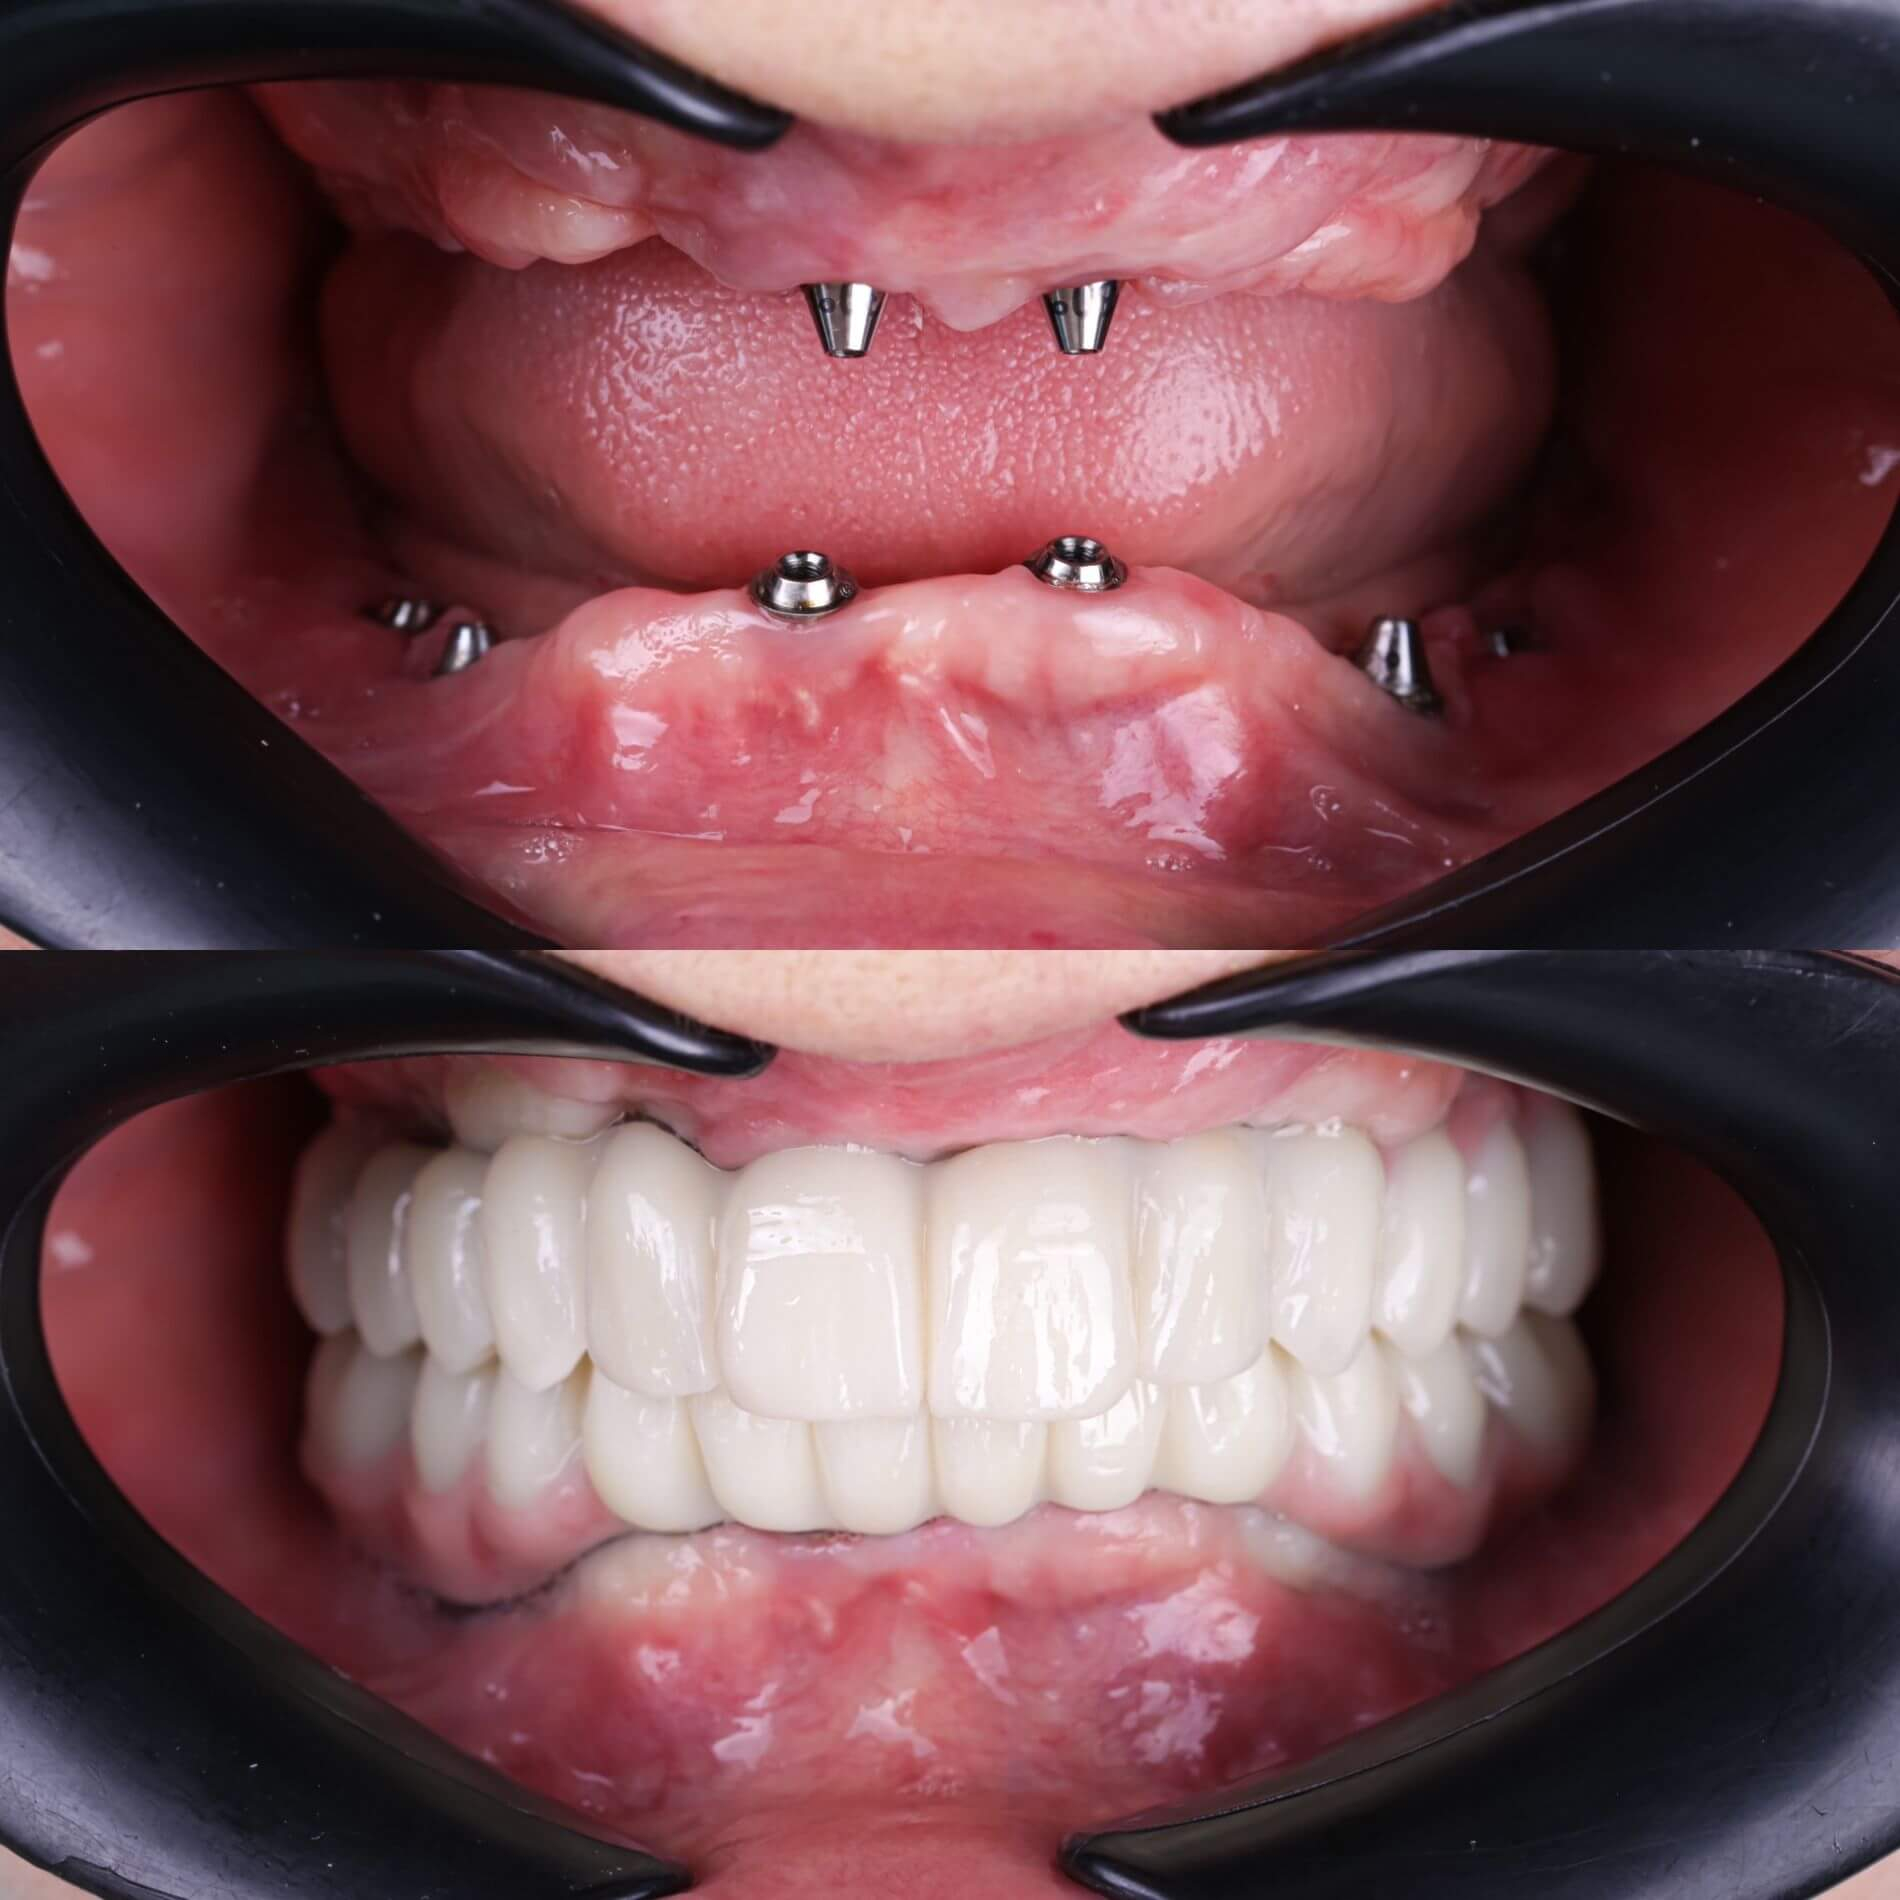

Галерея